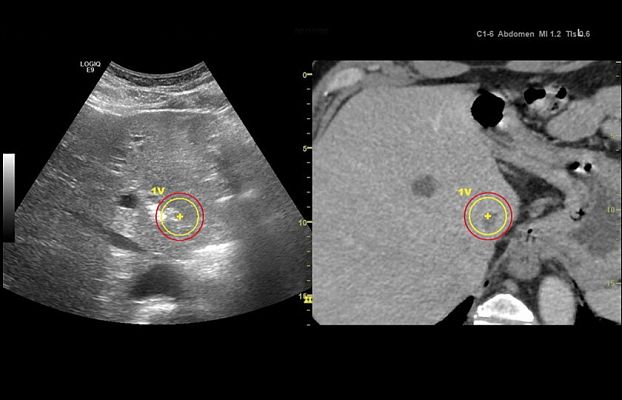

Клинические изображения

LOGIQ E9 XDclear 2.0 — это непревзойденные возможности диагностики при проведении ультразвуковых исследований у пациентов любой комплекции и возраста. Система позволит получить достоверные результаты как при сканировании технически сложных пациентов с избыточным весом, так и для новорожденных с небольшой массой тела.

В новой версии системы были модернизированы практически все элементы, отвечающие за процесс формирования изображений — от сигнальных последовательностей датчиков до алгоритма повышения четкости на уровне отдельных пикселей, в результате платформа XDclear 2.0 позволяет получить более высокое разрешение одновременно с увеличенной глубиной проникновения.

LOGIQ E9 XDclear 2.0 — это непревзойденные возможности диагностики при проведении ультразвуковых исследований у пациентов любой комплекции и возраста. Система позволит получить достоверные результаты и при сканировании технически сложных пациентов с избыточным весом, и для новорожденных с небольшой массой тела.

В новой версии системы были модернизированы практически все элементы, отвечающие за процесс формирования изображений — от сигнальных последовательностей датчиков до алгоритма повышения четкости на уровне отдельных пикселей, в результате платформа XDclear 2.0 позволяет получить более высокое разрешение одновременно с увеличенной глубиной проникновения.

Благодаря усовершенствованной акустической архитектуре, более мощной подсистеме постобработки и высоконтрастному OLED-монитору удалось значительно улучшить рабочие характеристики устройства по сравнению с предыдущей версией.

- Существенное повышение контрастности более чем на 20% даёт возможность различать даже самые небольшие детали на изображении.

- Вдвое увеличенное пространственное разрешение позволяет производить идеальную фокусировку.

- Больший охват — на 170% больше полезной информации на экране.